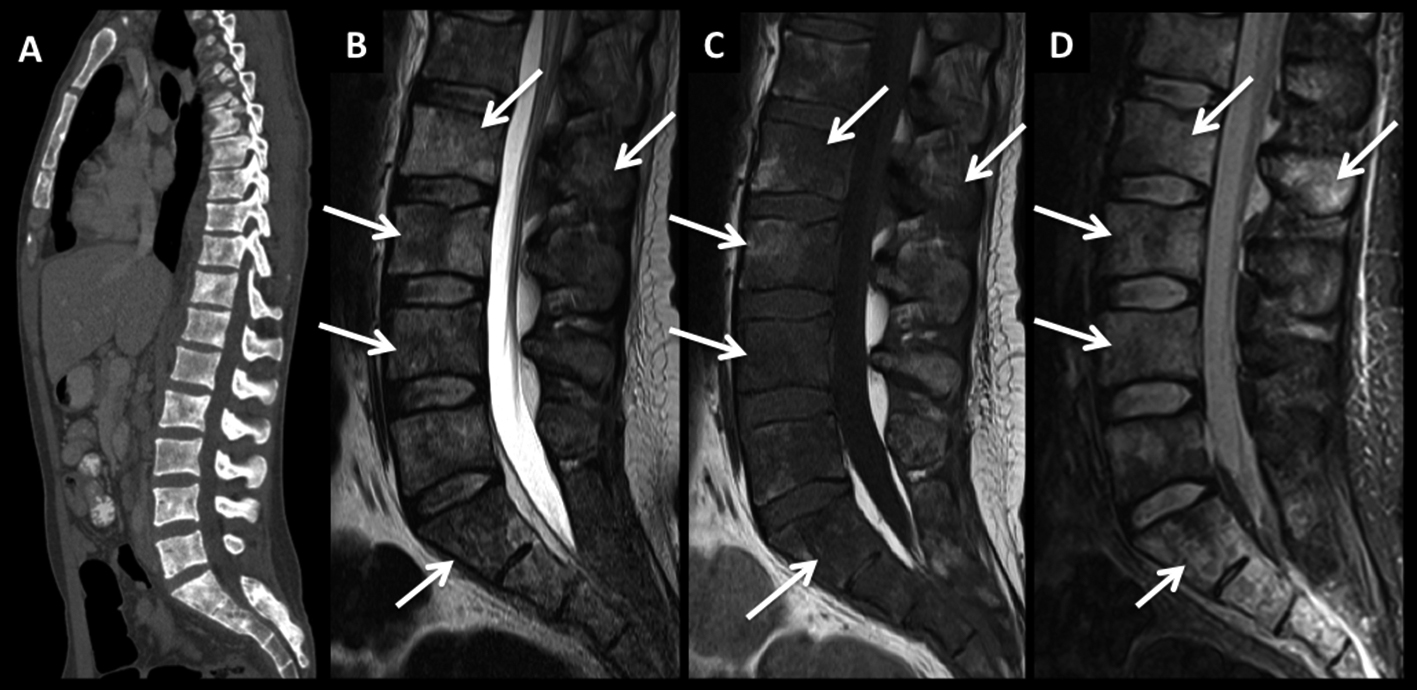

Figura 3

LNH, lesión ósea única, compromiso secundario. (cont)

En el paciente se observa un patrón de lesiones múltiples de sustitución con un patrón infiltrativo. En la TC plano sagital (A) se observa un aumento difuso, parcheado de la densidad, sin aplastamientos vertebrales.

En RM, secuencia T2 sagital (B) las lesiones están mal definidas con alta señal, hipointensas en secuencia T1 (C) y edema en secuencia STIR (D).

Este patrón, menos frecuente, tiene diferentes diagnósticos diferenciales, sobre todo con el mieloma múltiple.

Figura 4

LNH, lesiones óseas y masa extradural, compromiso secundario.

Paciente con LNH sistémico, que presenta dolores óseos progresivos y un síndrome de medular asociado.

En RM, secuencia T2 sagital (A) se observan múltiples pequeñas lesiones óseas (*) heterogéneas, y una masa de partes blandas a nivel dorsal bajo, intra-raquídea, extradural, de baja señal en T2 con desplazamiento y compresión del cordón medular (flecha discontínua).

En secuencia T1 (B) es de baja señal y luego de administrar contraste presenta intenso realce, homogéneo (C).

LNH, lesiones óseas y masa extradural, compromiso secundario. (cont)

En el plano axial (D secuencia T2, E secuencia T1 y F secuencia T1 con contraste) se observa la masa descrita con un patrón de crecimiento que lo “amolda” al canal y se extiende a los espacios vecinos a través de los neuro-forámenes del nivel seleccionado.